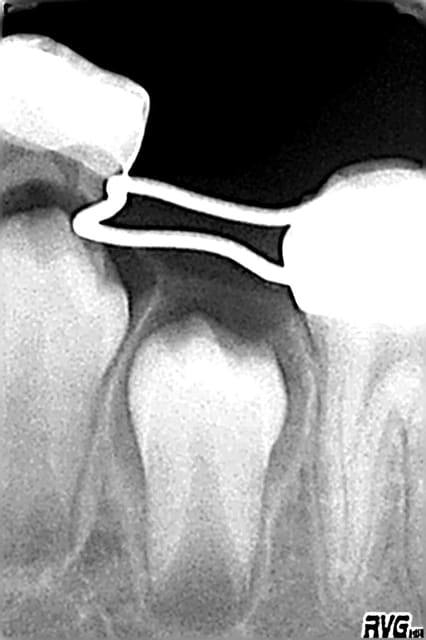

en 2006 ext de 75 et pose d'un mainteneur

en 2007 ext de 85 secteur où j'ai fait 2 erreurs:

1)ne pas mettre de couronne pedo en 2004 et me contenter d'un CVI(d'ou reprise de carie)

2)lors de l'extraction ne pas avoir mis de mainteneur d'espace au vu de la radio qui montrait 45 pas si loin...

et il manque de la place ,pas gd chose mais il manque!(photo en octobre et photo en janvier: pas de changement:c'est bloqué!)

mais comme quoi un mainteneur n'est pas inutile

85 en 2007 umqpaf - Eugenol

Radio75 s16u0c - Eugenol